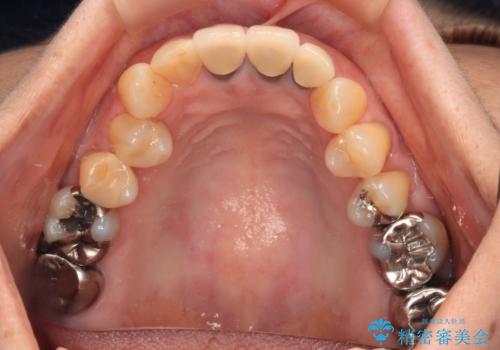

- 黄色みのある前歯のセラミックを、明るい色に替えたいとのことで来院された患者様です。

透明感がないことも気になっていたため、オールセラミッククラウンでは透けてしまう可能性のある金属の土台をファイバーコアに置き換え、1トーン明るいクラウンにて仕上げていくこととしました。